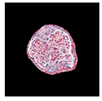

| True label: Mesangioproliferative |  |  |  |  |  |

| single-multiclass: Mesangioproliferative p = 0.935, IoU = 0.029 | |||||

| multiple-binary: Mesangioproliferative p = 0.988, IoU = 0.032 | |||||

| spatially guided: Mesangioproliferative p = 0.873, IoU = 0.201 |